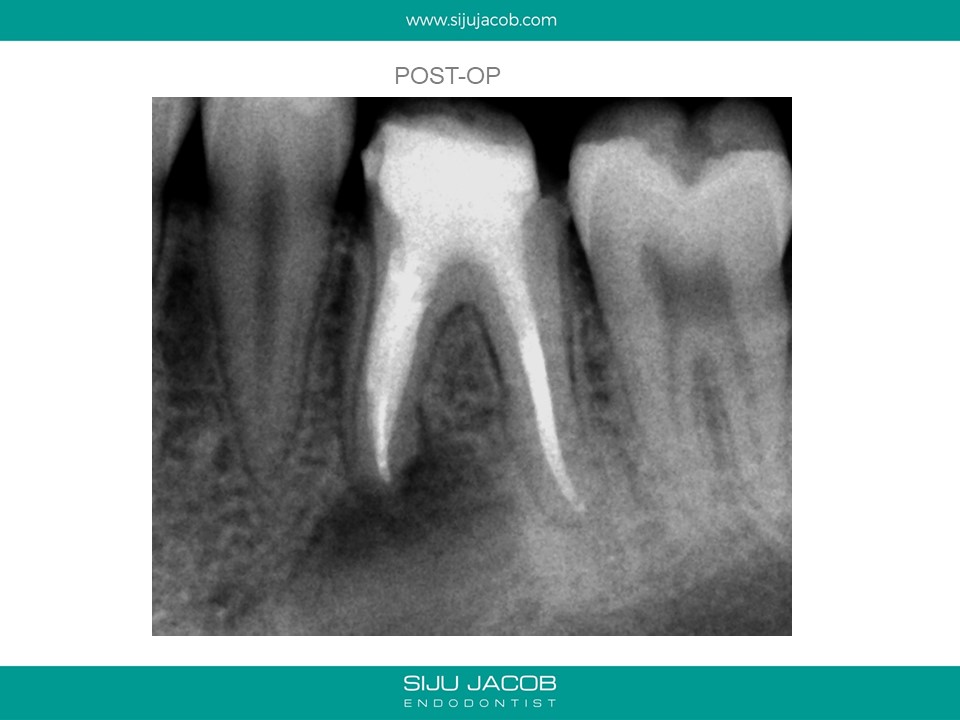

This is a case from 12 years ago. I re-treated all the canals including the distal which had a metal post. At, the one-year recall, the mesial root seems to have healed well. Today, I would probably have left the distal root alone and not over-enlarged those mesial canals.